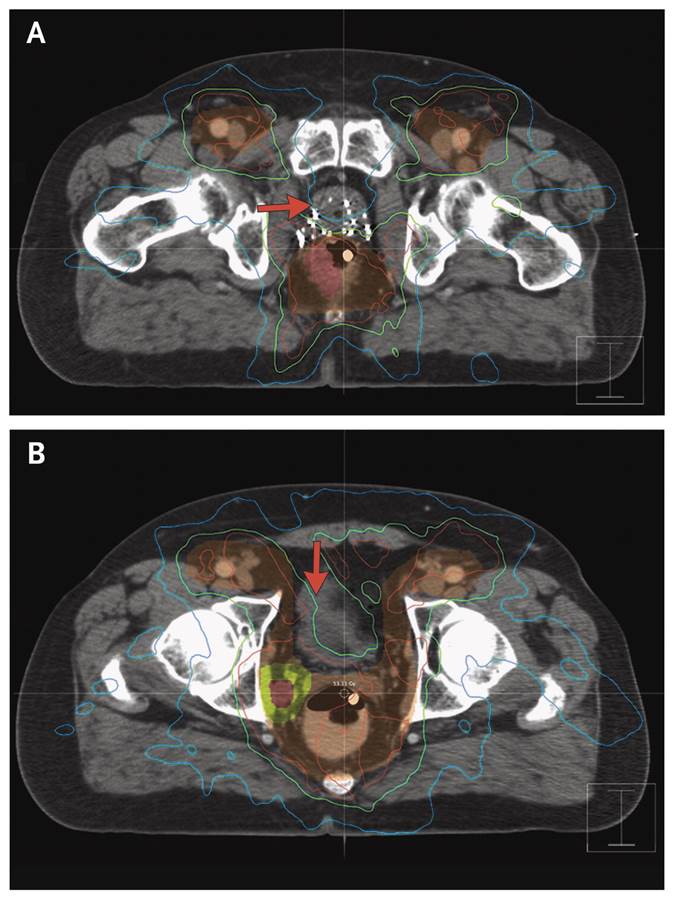

Case Record of the

#MGH: Year-Old Man with Rectal Bleeding and a History of#ProstateCancer http://nej.md/2hamqjr pic.twitter.com/VX3RA4VInT